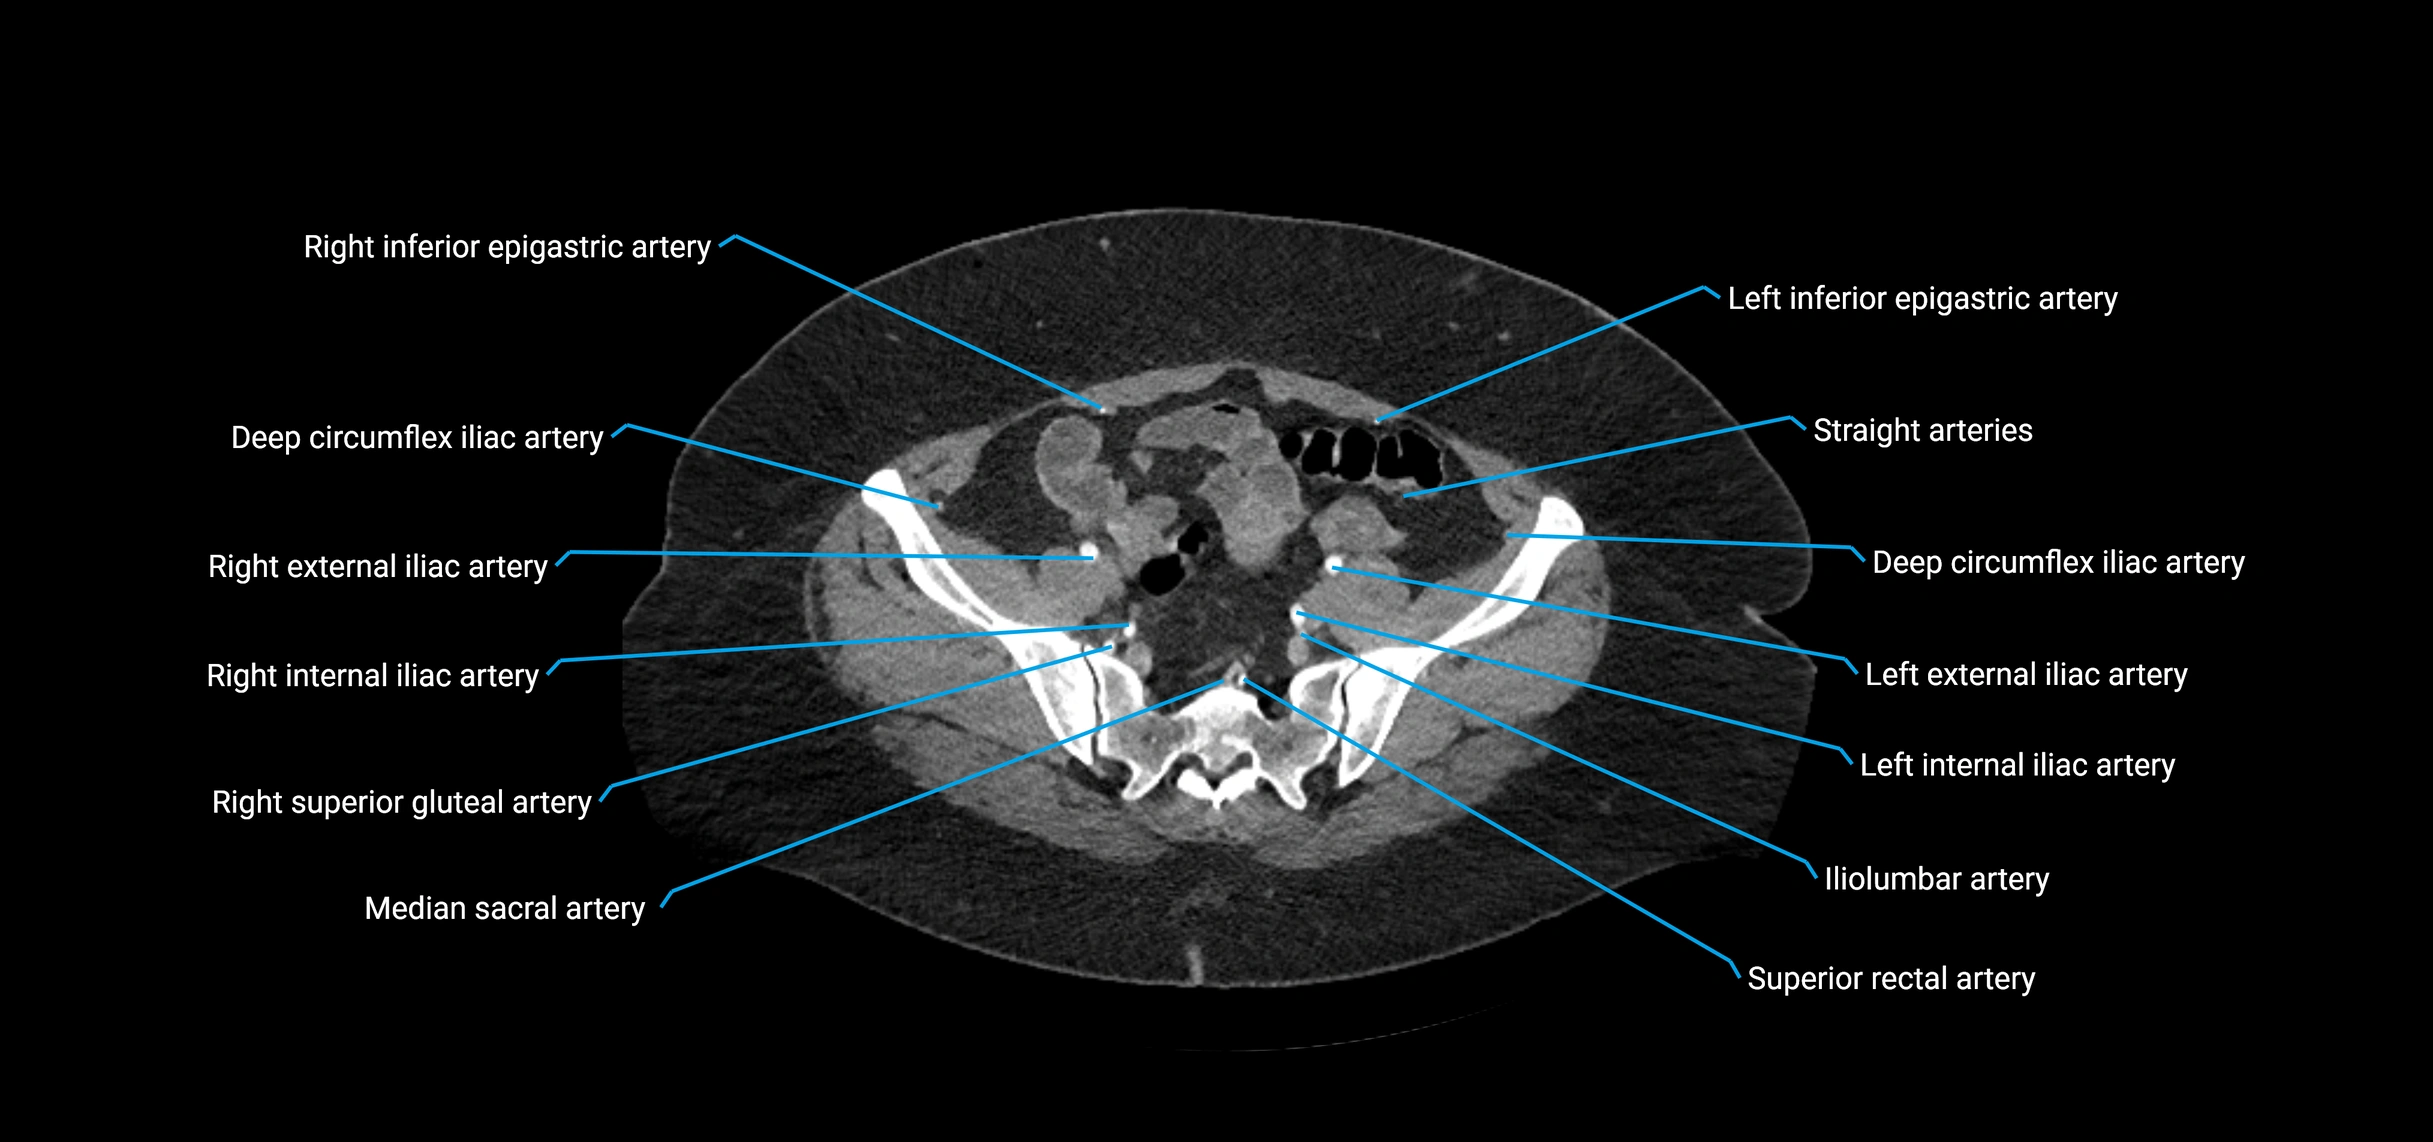

Contrast-enhanced CT (CTA):

• Gold standard for abdominal aortic imaging

• Provides excellent detail of lumen, wall, aneurysm, thrombus, and branch vessels

• Multiplanar and 3D reconstructions help in aneurysm measurement, stent graft planning, and dissection evaluation

• Detects acute rupture, traumatic injury, or occlusion with high sensitivity